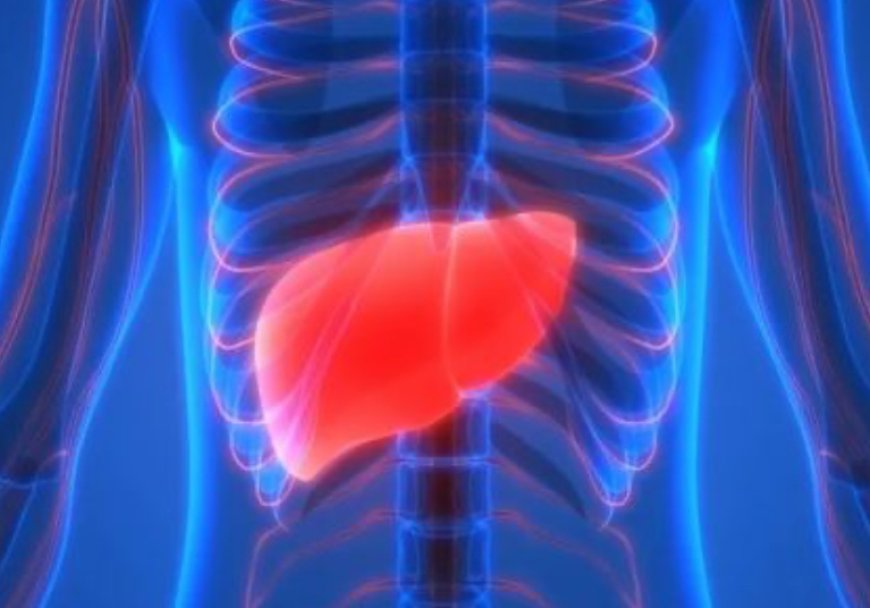

المركز الإفريقي لمكافحة الأمراض: مرض التهاب الكبد يعد “القاتل الصامت” في إفريقيا

قال المركز الإفريقي لمكافحة الأمراض، إن مرض التهاب الكبد يعد القاتل الصامت في إفريقيا.

وأكد المركز أن هذا المرض يتسبب في وفيات أكثر من (الأيدز) و(الملاريا) و(السل).

ويتبنى المركز الإفريقي لمكافحة الأمراض هدف القضاء على مرض التهاب الكبد في القارة بحلول عام 2030.

وكانت دراسة علمية حديثة، قد حذرت من أن حالات الإصابة بسرطان الكبد قد ترتفع بشكل كبير بحلول عام 2050، حيث تتوقع أن تقفز من 870 ألف حالة سنويا إلى 1.52 مليون حالة في جميع أنحاء العالم، ما لم تبذل جهود مكثفة للحد من العوامل المسببة القابلة للوقاية، مثل السمنة والتهاب الكبد الفيروسي.

ونُشرت الدراسة، التي أوردتها مجلة «لانسيت» الطبية، في اليوم العالمي لالتهاب الكبد، مشيرة إلى أن سرطان الكبد، سادس أكثر أنواع السرطان شيوعا وثالث أخطرها، وقد يودي بحياة 1.37 مليون شخص بحلول منتصف القرن، وفقا لموقع «ساينس أليرت».